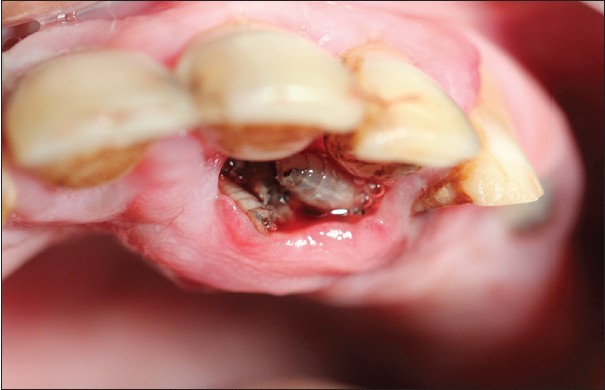

What is Oral Myiasis?

‘Oral’ means something related to the mouth, and it can be related to teeth, gums, tongue, and maxillary Sinus.

Maxillary Sinus is crucial in dentistry; it is located inside the skin in the facial bone below the eyes and front of the ear, and it’s an air cavity lined by cells.

It transfers infection from teeth and oral cavity towards the brain, nose, and vice versa. Sinuses have close relations with the upper 2nd Molars of each side.

‘Myiasis’- It has 2 Greek words, ‘Myia’ means fly insects that fly and ‘as is’ means disease. Flies hatch their larvae (their eggs) on the dead tissue. The larva eats the dead tissue and gets it’s nourishment from it and turns into an adult insect and flies away.

So, Oral Myiasis is a rare disease caused by the Larvae of dipterans. It is reported mostly in developing countries. Myiasis can occur in various parts of our body, not only in the oral region. It can be in the skin, nose, ear, eyes.

What Are The Causes Of Oral Myiasis?

It is caused by flies of order Dipterans, as previously said. Sarcophagidae, Calliphoridae, Oestridae, and Muscidae are genera from the order Dipterans.

Those were some examples of genera. Mostly, it is Chrysomya bezziana (Old Screwworm or Screwworm). It is an obligate parasite; it needs some dead tissue for its species survival, propagation, and reproduction. Its female lays eggs in open wounds, ulcers, scratches, or mucous membranes.

Suppose any injury or cut occurs and remains in direct contact with the air and external environment or not banded properly in its treatment. In that case, it serves as an open wound. Ulcers happen when stomach acid damages the lining of the digestive tract. The mucous membrane is the skin and gingival of the mouth.

This disease three modes of infestation:-

Accidental: when larvae ingested along with food.

Semi specific: larvae are laid on necrotic tissue.

Obligatory: larvae affect intact skin.

Treatment Of Oral Myiasis:

We highly recommend you take the patient to a concerned dental surgeon for treatment as soon as you observe symptoms. It will be good if treatment is done early to contain its infection.

However, the treatment is the surgical removal of larvae. And the result of the activities of larvae is treated after its removal. Turpentine solution help in the extraction of maggots.